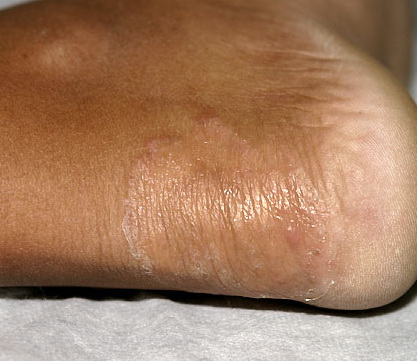

Chronic Hyperkeratotic Type.

Usually bilateral with patchy or diffuse scaling limited to the thick skin, soles, and the lateral and medial aspects of the feet, this is also known as “moccasin-type” tinea pedis. T. rubrum, the most common etiology, produces very few minute vesicles, leaving collarettes of scale less than 2 mm in diameter. Erythema is variable.